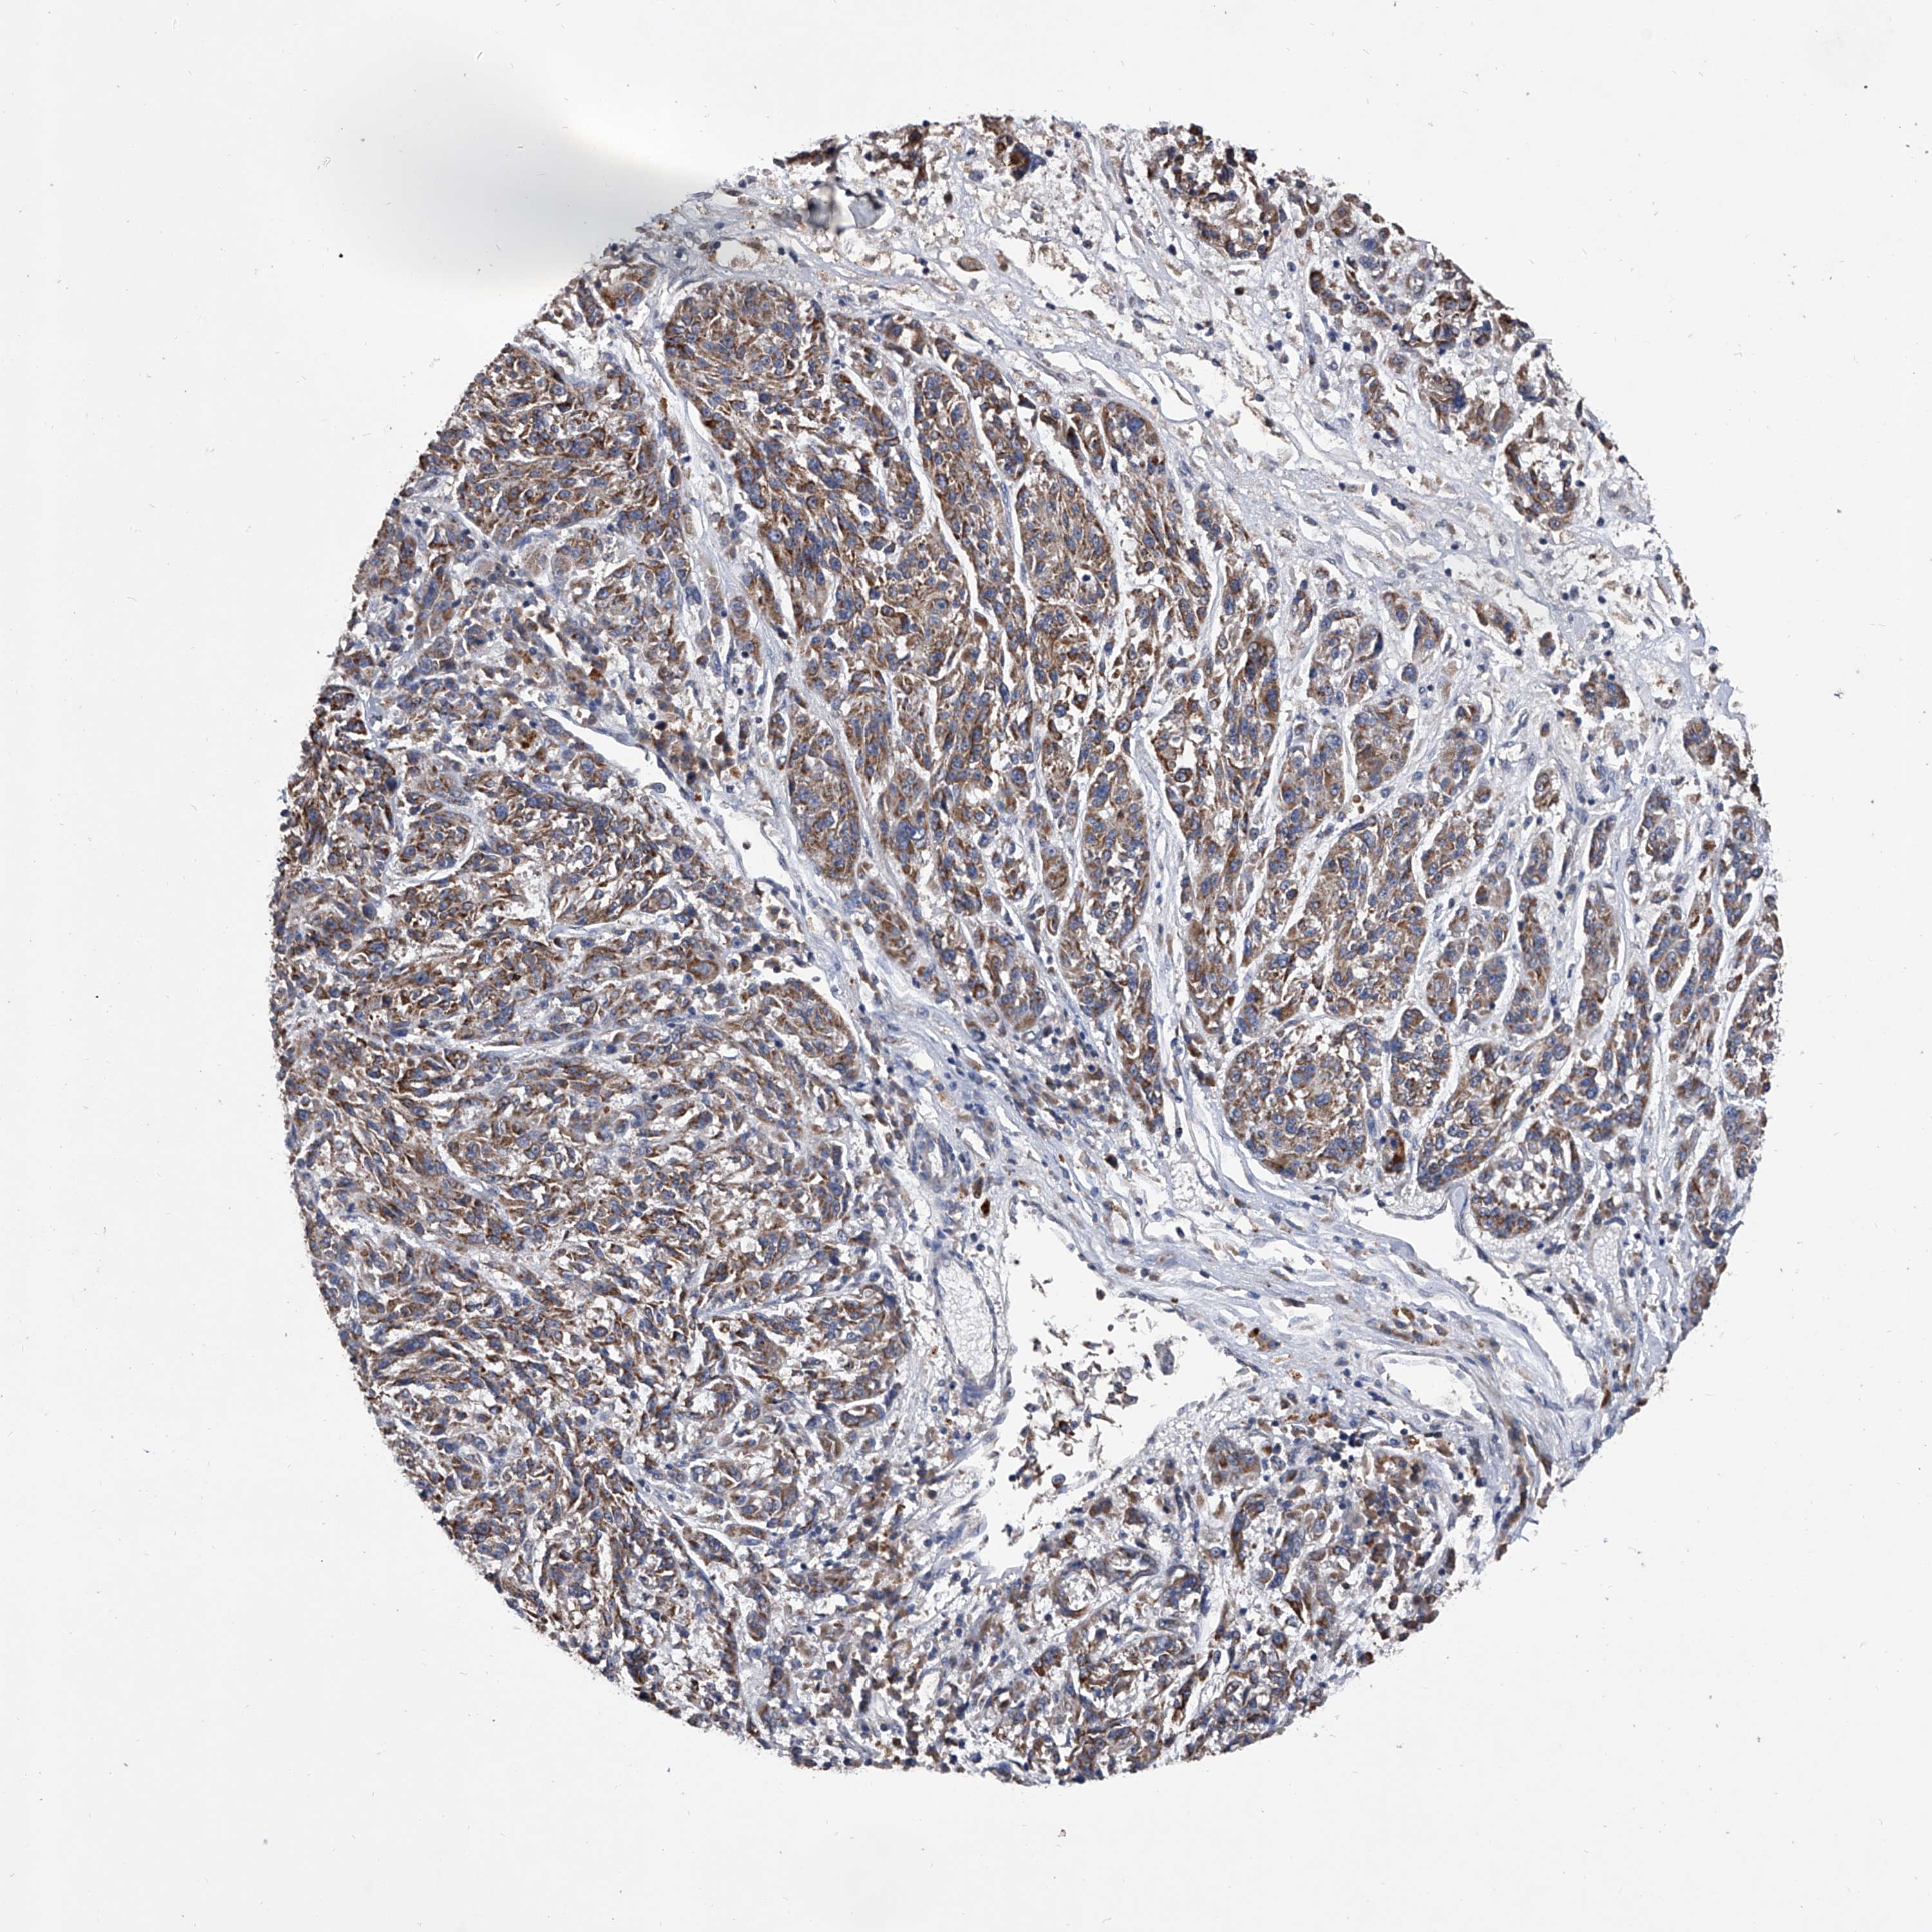

MELANOMA - Protein expressioni

A mouse-over function shows sample information and annotation data. Click on an image to view it in a full screen mode. Samples can be filtered based on level of antibody staining by selecting one or several of the following categories: high, medium, low and not detected. The assay and annotation is described here.

Note that samples used for immunohistochemistry by the Human Protein Atlas do not correspond to samples in the TCGA dataset.

Antibody stainingi

Antibody staining in the annotated cell types in the current human tissue is reported as not detected, low, medium, or high, based on conventional immunohistochemistry profiling in selected tissues. This score is based on the combination of the staining intensity and fraction of stained cells.

Each image is clickable and will lead to virtual microscopy that enables deeper exploration of all samples and also displays staining intensity scores, fraction scores and subcellular localization as well as patient and tissue information for each sample.

Antibody HPA030278

Antibody CAB004511

Staining

High

Medium

Low

Not detected

Intensity

Strong

Moderate

Weak

Negative

Quantity

>75%

75%-25%

<25%

None

Location

Nuclear

Cytoplasmic/membranous

Cytoplasmic/membranous,nuclear

Malignant melanoma, NOS

Malignant melanoma, Metastatic site